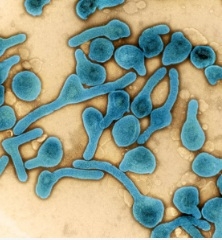

शोधकर्ताओं ने चूहों में विकसित एंटीबॉडी का सफलतापूर्वक परीक्षण करने के बाद, एपस्टीन-बार वायरस से बचाव करने...